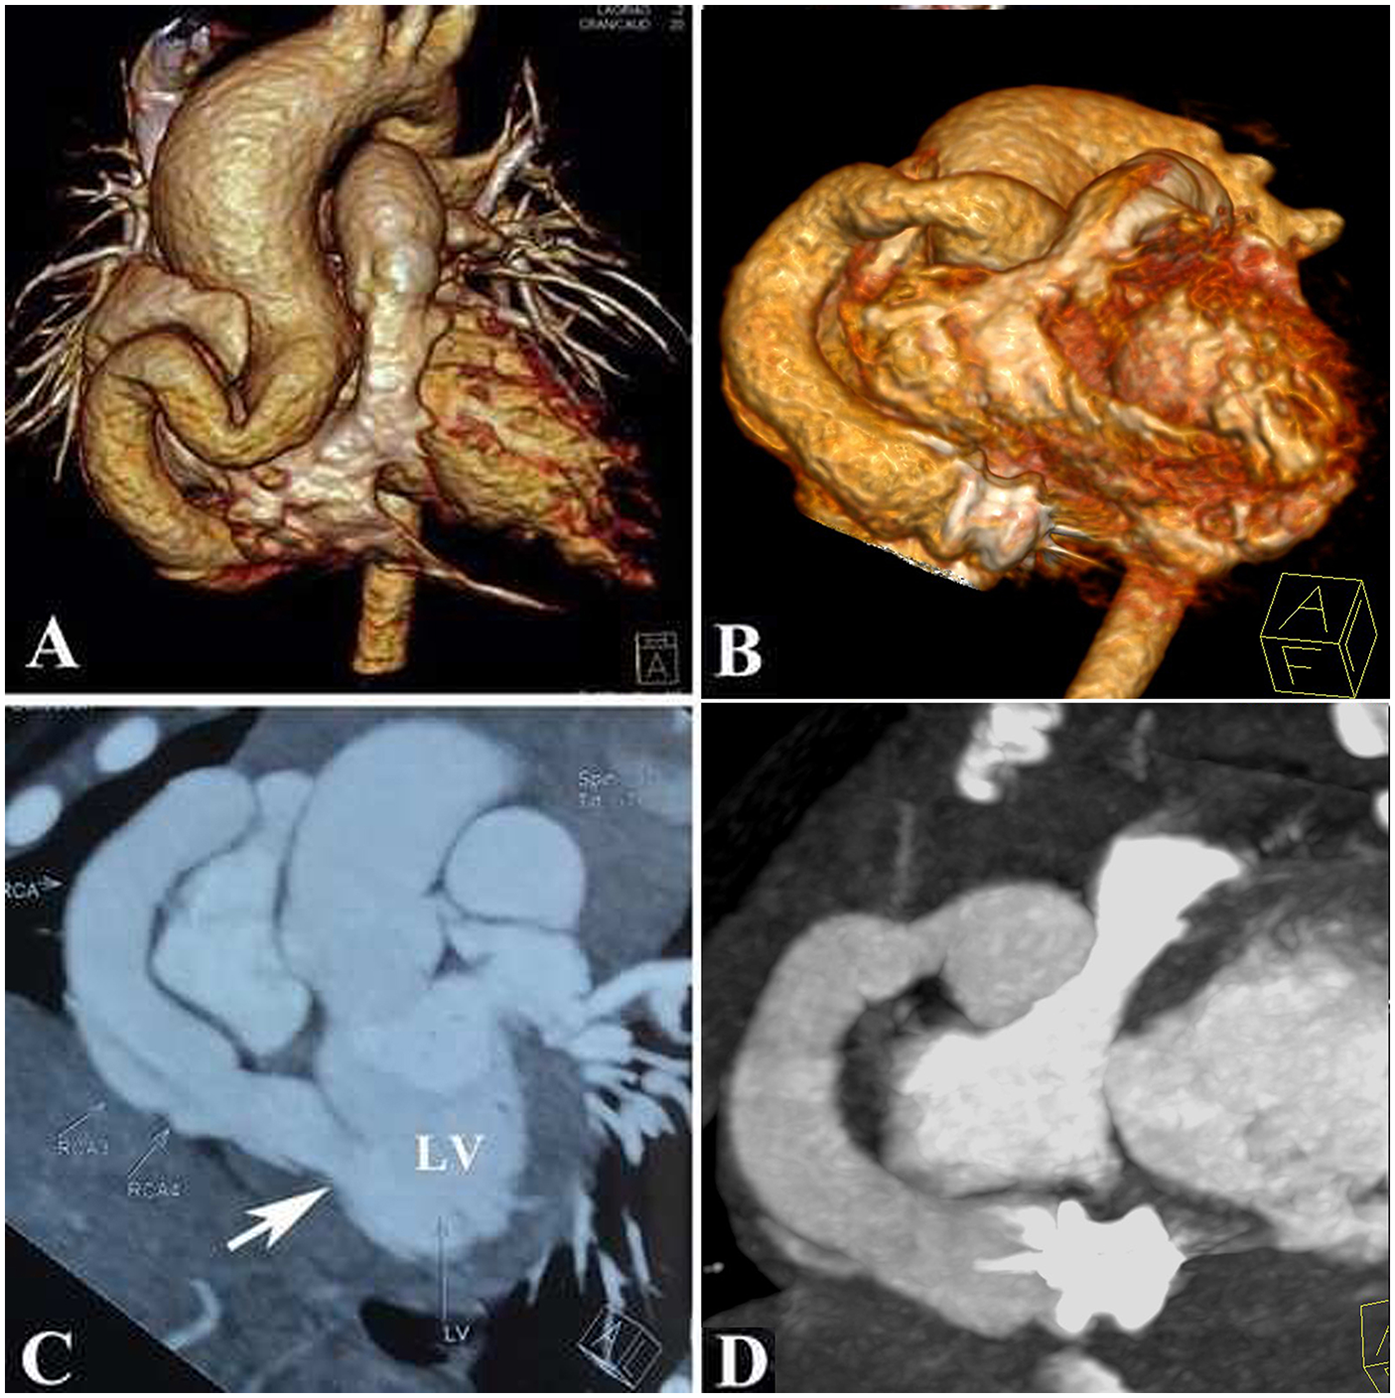

At the 3-month follow-up, computed tomography angiography, and echocardiography showed decreased LV size, excellent device positioning, and complete CAF occlusion without thrombus formation (Figure 4). The RCA had no branches; therefore, we discontinued the aspirin after a departmental meeting. By 6 months, optimal remodeling was achieved, as evidenced by imaging studies (Supplementary Video S3). Troponin I levels and electrocardiograms remained normal during 10 years of follow-up, with no ST-T segment abnormalities observed. A short video demonstrates how the procedure is carried out (Supplementary Video S4).

Figure 4

Anatomy of the coronary artery fistula showed by a computed tomographic angiography: (A,C): Pre-procedure; (B,D): Post-procedure.